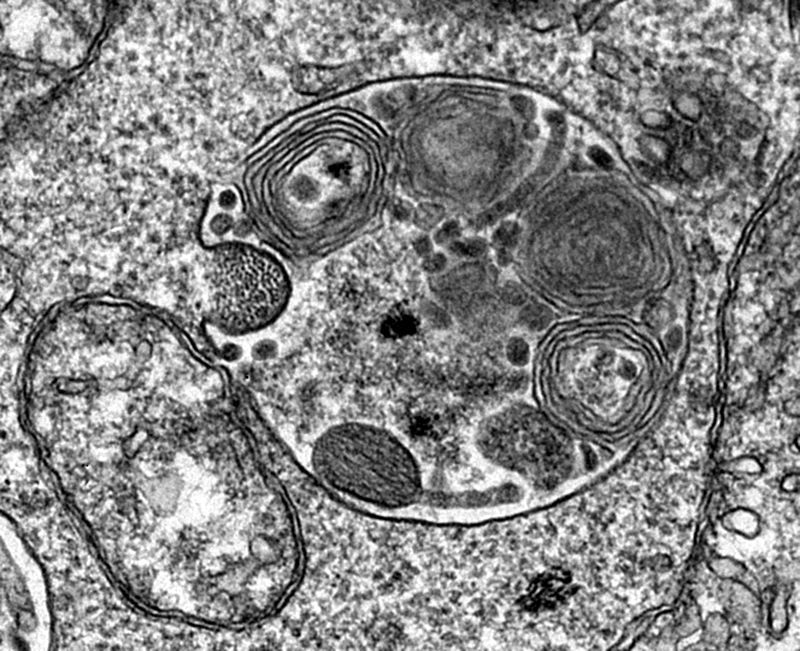

The PhD program in Cell Biology and Biomedicine trains researchers capable of contributing to the knowledge about the normal and pathological functioning of the cell and apply this knowledge to understand and control diseases that require better treatments or lack of treatment.